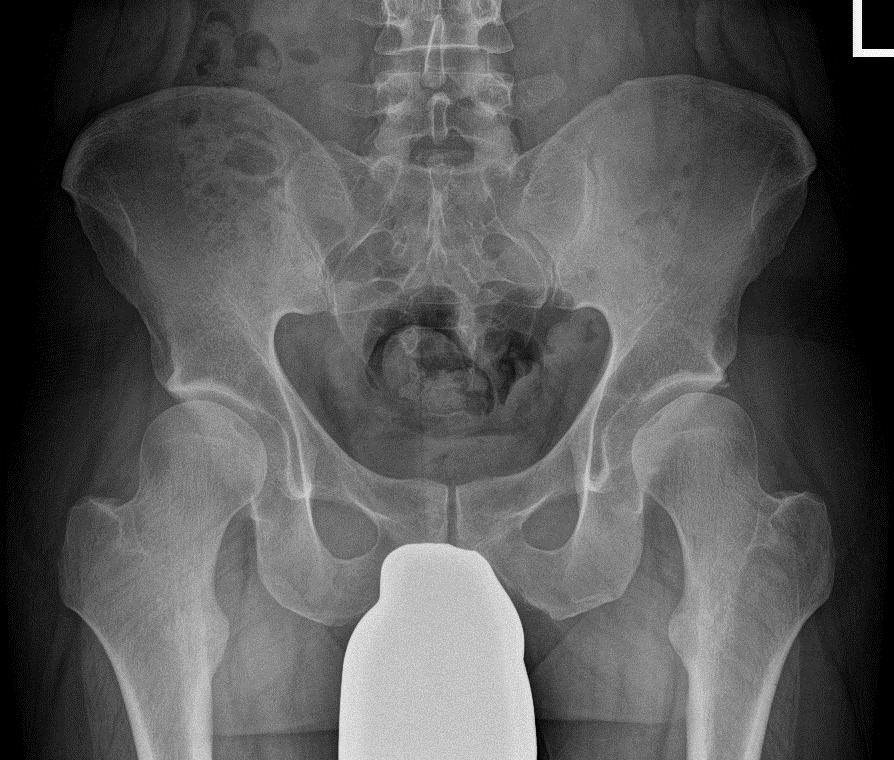

Highquality radiographs must be obtained to enable an accurate assessment of the degree of acetabular dysplasia and allow for precise determination of the optimal amount of acetabular correction. An anteroposterior pelvic overview in proper rotation and tilt, a Dunn lateral view (e.g., 45-degree projection) and a false profile (faux profile) view of the affected hip should be performed. To estimate the amount of postoperative correction, the congruency between acetabulum and the femoral head ability and containment of the femoral head and additional radiograph in functional abduction and internal rotation should be obtained.

The radiological criteria for a DDH are currently defined as a lateral CE-angle of less than 23°. Other radiological markers are an acetabular index greater than 14° and a femur extrusion index greater than 27° 4. Prior to surgery the authors recommend a digital planning to determine the optimum amount of acetabular reorientation and avoid over- or under-correction (Fig. 1) in anteroposterior pelvic overview. This is done using the identical digital 2D planning software for arthroplasty procedures (TraumaCad, BrainLab, Munich). On the anteroposterior pelvic overview, a postoperative LCE angle of 30°, a positive acetabular index, a femoral extrusion index ≤ 25% and an anteverted acetabulum are the target values for correction.